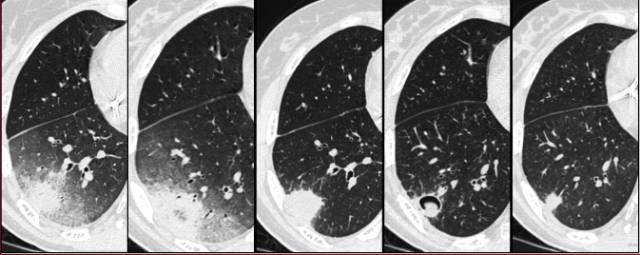

图4 曲霉病治疗后,肺内病灶的自然进程。第4张图可见空气新月征

恢复期(开始治疗后的2~3周,诊断早期意义不大)常见的另一个影像征象是空气新月征,来自于毗邻肺实质坏死肺碎片分离。